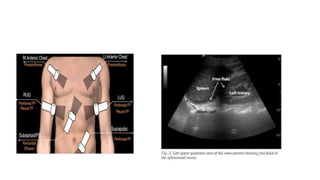

FOCUSED ABDOMINAL SONOGRAPHY IN

TRAUMA (FAST)

• The primary objective of focused abdominal sonography in trauma

(FAST) - to identify the presence of haemoperitoneum

• Indications of FAST

• Haemodynamically unstable patients with suspected abdominal

injury.

• Significant extra-abdominal injuries (orthopaedic, spinal, chest)

requiring a non-abdominal emergency surgery.

• The presence of free intraperitoneal fluid or solid organ injury is

considered as a positive FAST .

FOCUSED ABDOMINAL SONOGRAPHYIN TRAUMA (FAST) • The primary objective of focused abdominal sonography in trauma (FAST) - to identify the presence of haemoperitoneum • Indications of FAST • Haemodynamically unstable patients with suspected abdominal injury. • Significant extra-abdominal injuries (orthopaedic, spinal, chest) requiring a non-abdominal emergency surgery. • The presence of free intraperitoneal fluid or solid organ injury is considered as a positive FAST .